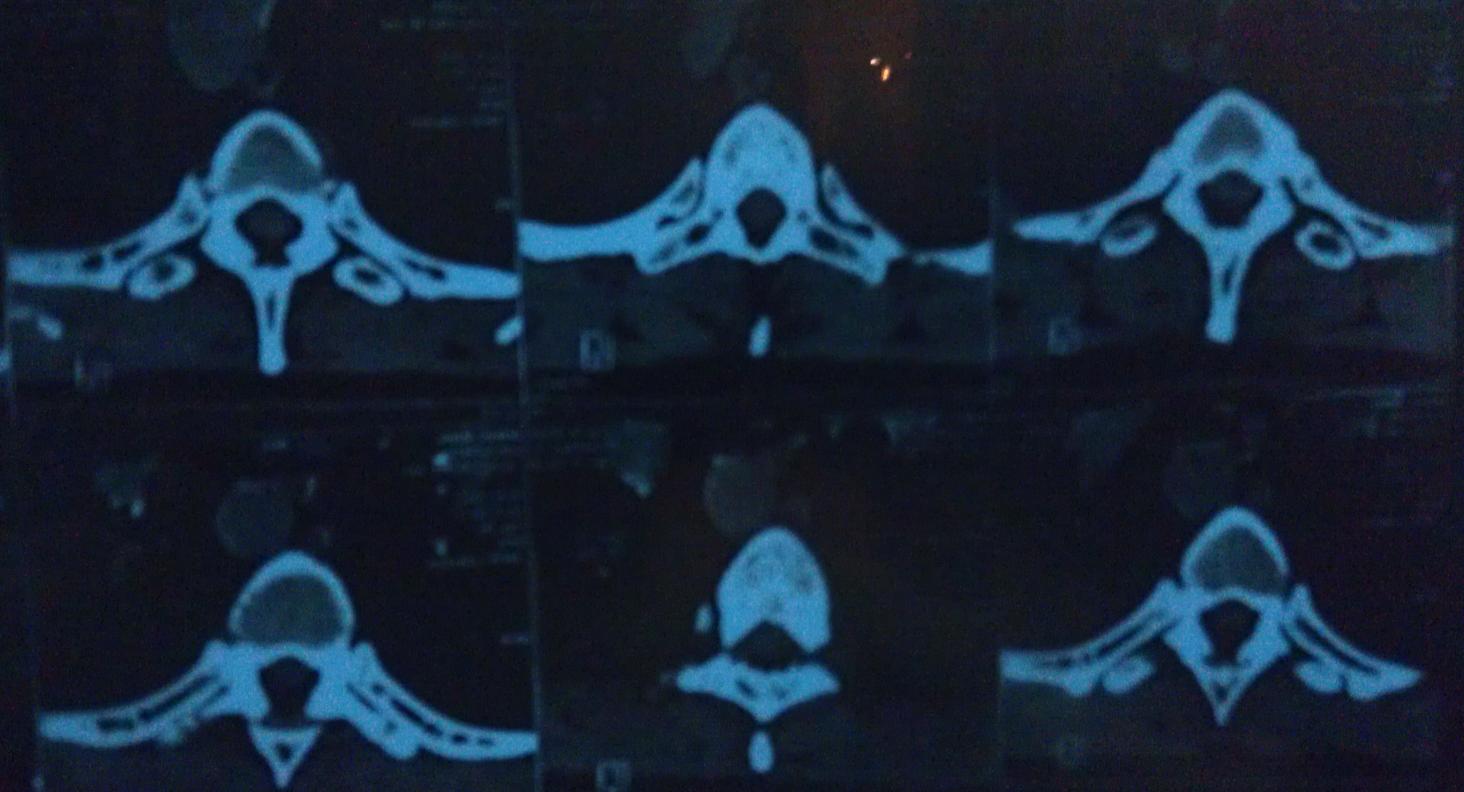

При томографии обнаружили мелкоячеистый остеопороз позвонков.

Я так понимаю, что всё что темное в позвонках - это пустоты, а должно быть сплошным белым цветом?

Вложение 988Вложение 989Вложение 990